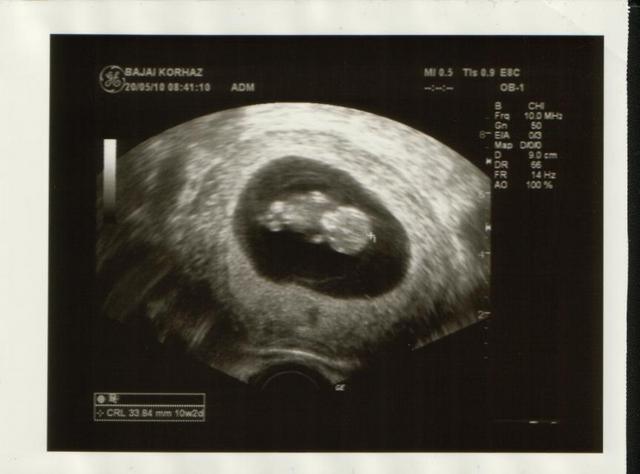

Annus: a 10 hetes UH-on nekem is 28mm volt a babó!